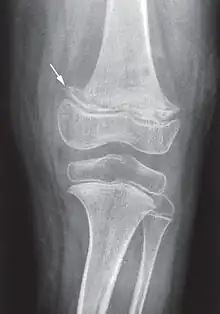

Elle débute par une perte d'appétit, un arrêt de la prise de poids, une pâleur, suivis d'un syndrome douloureux des membres entraînant agitation, cris et insomnie (pleurs à la mobilisation des membres). Les signes osseux sont au premier plan : à la palpation douce, on trouve des tuméfactions osseuses, surtout au niveau du fémur ou des articulations chondrosternales (entre le sternum et les côtes, parfois appelées le « rosaire scorbutique »). La gingivite n’apparaît qu'avec les premières poussées dentaires[19].

Les douleurs osseuses sont liées aux hémorragies sous-périostées. La radiographie peut montrer les troubles du périoste (hématomes sous-périostés) et de la structure osseuse (ostéoporose avec aspect en « verre pilé », la « ligne scorbutique » séparant la diaphyse des extrémités, élargissement de l'extrémité antérieure des côtes...)[19].